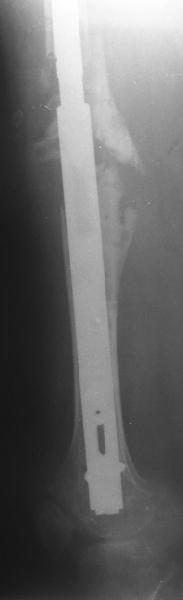

Female, rheumatoid, THA in 2003, car accident in 2006, failed plating. Nailing in Oct 2007. The nail is solid with hollow proximal part where the stem is docked. Last images are in 1 year after

nailing.

Спасибо за обсуждение. После нескольких дней тракции аппаратом сделали. Попытка закрытой репозиции не удалась из-за смещения по ширине, мешали фрагменты цемента. После их удаления репозиция получилась. Еще убрали немного цемента с ножки по латерльной стороне, чтобы обнажить 40-50 мм ее дистальной части, для плотной посадки гвоздя. Дальнейшее введение гвоздя было несложным. Протез показался нам стабильным в проксимальной части как латерально, так и медиально. Картинки в приложении.

THX for the discussion. After few days of traction by ex-fix the surgery was performed. An attempt of closed nailing was unsuccesful because of fragment translation, which was blocked by cement fragments. After removal of broken cement pieces reduction was reached "automagically". Also some cement from lateral part was removed by

chisel to expose distal 40-50 mm of the stem to allow tight fit of the nail. Further fixation by the nail was pretty easy and straightforward. Images attached. The stem looked stable in its proximal part both laterally and medially. Comments/critics are welcome.